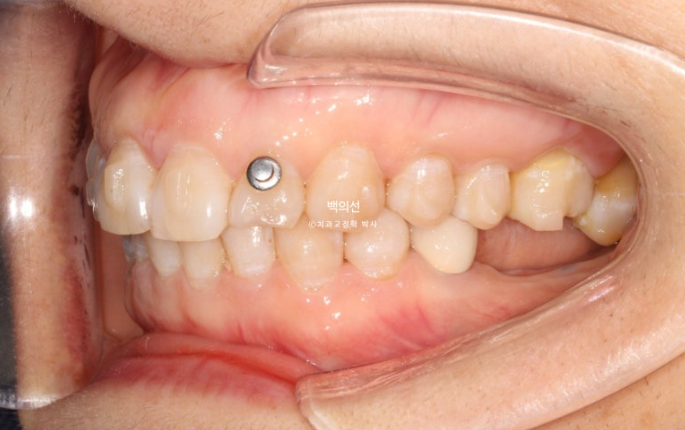

작년 9월, 앞니 돌출과 삐뚠치아 배열을 위해 오신 환자분입니다.

정면에서는 아래 앞니 일부가 윗니에 가려져 안 보일정도의 심한 과개교합을 보입니다.

좌측 아래는 어금니가 빠진 지 오래된 상태입니다.

단 빈공간으로 내려와 있는 큰어금니를 합입시킬때에는 교정용 나사가 필요합니다.

입천장에 교정용 나사인 미니스크류를 1개 심고 정출된 제1구치 함입을 도모합니다.